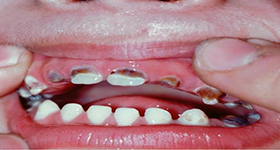

As a parent, we understand the concern you have for the health of your children’s dental health. We at Amrapali Dental Clinic work with you to minimize the amount of dental work your children will need as adults by taking an early, proactive approach in the maintenance of your child’s oral health. Dental care for children requires the services of a highly trained specialist, and your children will be met by our child care specialist (pedodontist) who will walk you and your children through the importance of oral hygiene for developing teeth. We will also evaluate the need for any type of space maintaining devices to avoid overcrowding in the future, which frequently reduces the need for future orthodontic braces. Amrapali Dental Clinic is a firm believer in the use of sealants, which are a protective coating placed on teeth which can prevent cavities on that tooth surface. Early visits to the dentist have the added benefit of making your child much less fearful of the dentist as an adult.

We also offer local, general and sedation anesthesia options for our young patients.